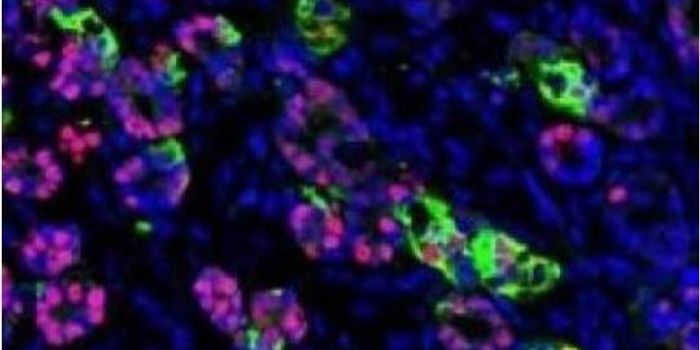

MAR 02, 2023CancerImmunotherapies, cancer treatments that target the immune system, have drastically improved patient care over the past d ...